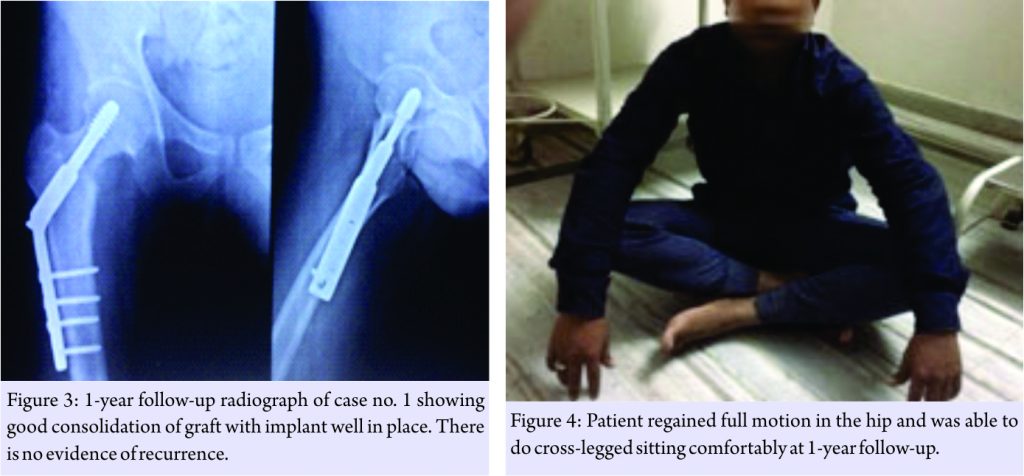

An en blocopen surgical resection of the lesion was planned under guidance of image intensifier. Procedurewas done in supine position. Standard anterior Smith Peterson approach was used for the exposure of formal neck. Inferomedial part of femoral neck was clearly seen on abducting and external rotating the hip. Lesion was localized and marked using image intensifier. Drill holes were made along the margin of the lesion. A large chunk of abnormal bone was osteotomized and removed. Complete excision of the lesion was confirmed. Size of the defect created was measured. Slightly oversized tricortical bone graft was taken from the ipsilateral iliac crestand impacted into the void with cortical surfaces facing outside. The graft was quite stable and does not require any additional fixation. Since the bone was removed from inferomedial aspect of femoralneck; to prevent fracture prophylactic fixation was done using dynamic hip screw and plate from a separate lateral incision. Excised bone was sent for histological examination. Patient has significant pain relief immediately postsurgery. The limb was non-weight-bearing for 2 weeks, followed by gradual weight-bearing with crutches as tolerated over a period of next 4 weeks. Patient returned to his previous activities of daily living after 2 months. The pathology report shows fibrous dysplasia, which the authors were not convinced with. Hence, it was decided to send the tissue and slides for repeat histological examination at another laboratory, which revealed multi nidi osteoid osteoma. Diagnosis of atypical osteoid osteoma was established after discussing with the pathologist. Follow-up at the end of 1 year did not show the presence of any residual symptoms or recurrences. Radiograph shows good consolidation of the graft with implant well in place (Fig. 3). Patient regained full motion in the hip and was able to do squatting and cross-legged sitting comfortably (Fig. 4).